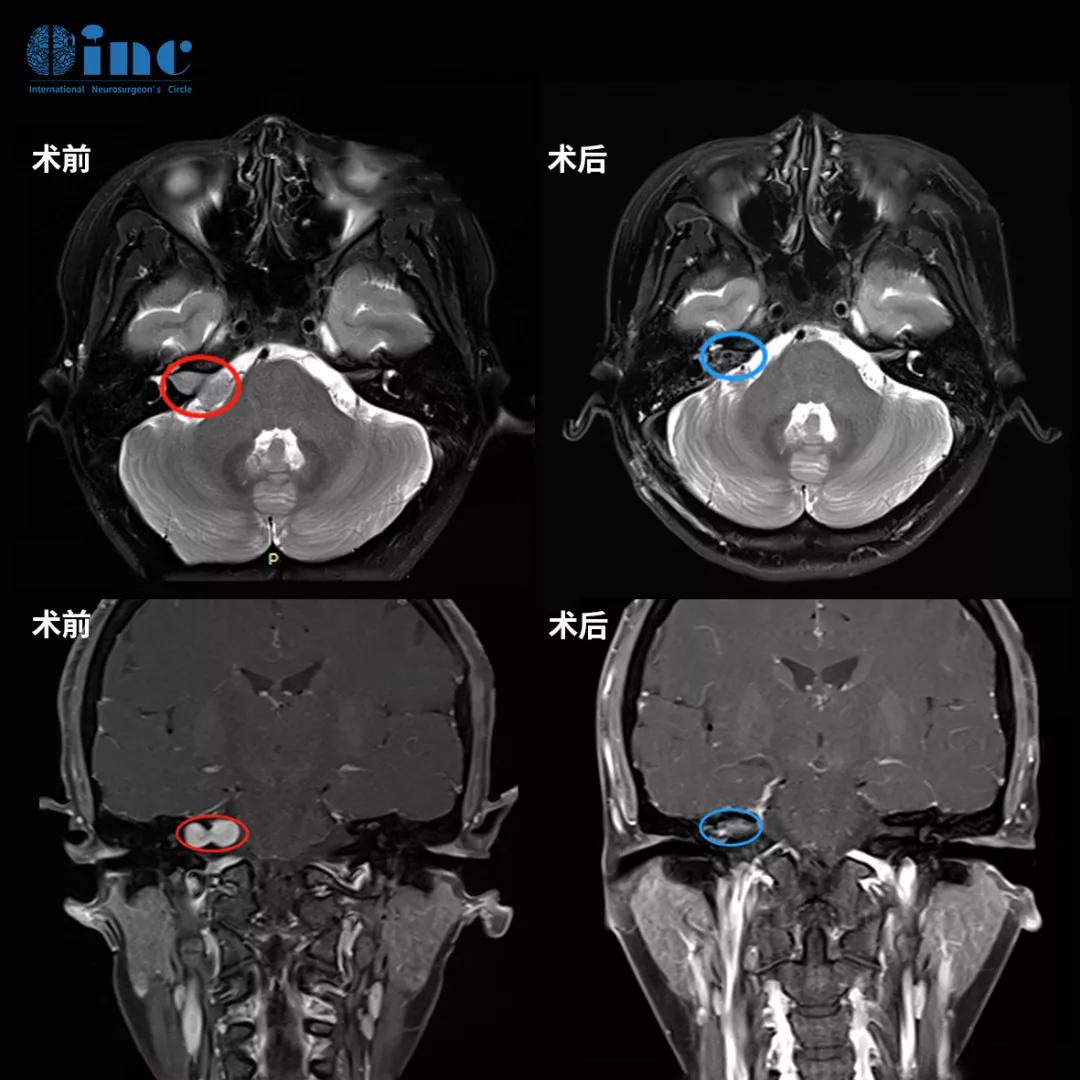

术前MR:姜女士颅脑MR提示听神经瘤病变,瘤体约2cm大小,但是有一部分完全生长于内听道骨质,压迫面听神经。

术后第2天转出ICU回到普通病房,且可下地行走,术后第3天可自主进食,术后1周出院,术后MR显示姜女士的听神经瘤得到全切,且听神经和面神经完好保留,无其他功能损伤和新发神经功能症状。没有术前一直恐惧和焦虑的耳聋、面瘫并发症,目前的姜女士正在逐渐回归工作生活正轨。

姜女士术前术后影像对比